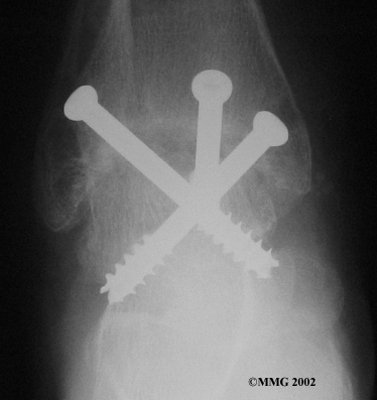

It is important when the surfaces are removed that the angles of the cut surfaces are correct. When the tibia is brought against the talus, the foot should be at a right angle to the lower leg. Once the cuts are made the bones must be held in place while they fuse. This can be done using large metal screws and metal plates if necessary. The screws are usually under the skin and are not removed unless they begin to rub and cause pain.

Inserting the screws

After ankle fusion, the physical therapists at FYZICAL Falmouth can help you learn to walk smoothly and without a limp. Although time needed for recovery varies among patients, an ankle brace will typically replace your cast after eight to 12 weeks. Your surgeon will take X-rays frequently to see if the bones are fusing together. You will probably need to use crutches during the time you wear the cast. As the fusion grows stronger, you will begin to put more weight on your foot when walking.